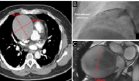

Se realizó una ecocardiografía para descartar endocarditis séptica, una complicación potencial de las infecciones por Staphylococcus aureus, la cual resultó normal. Los hemocultivos y el cultivo del líquido sinovial fueron positivos para Staphylococcus aureus sensible a oxacilina, confirmando el diagnóstico de costocondritis séptica.